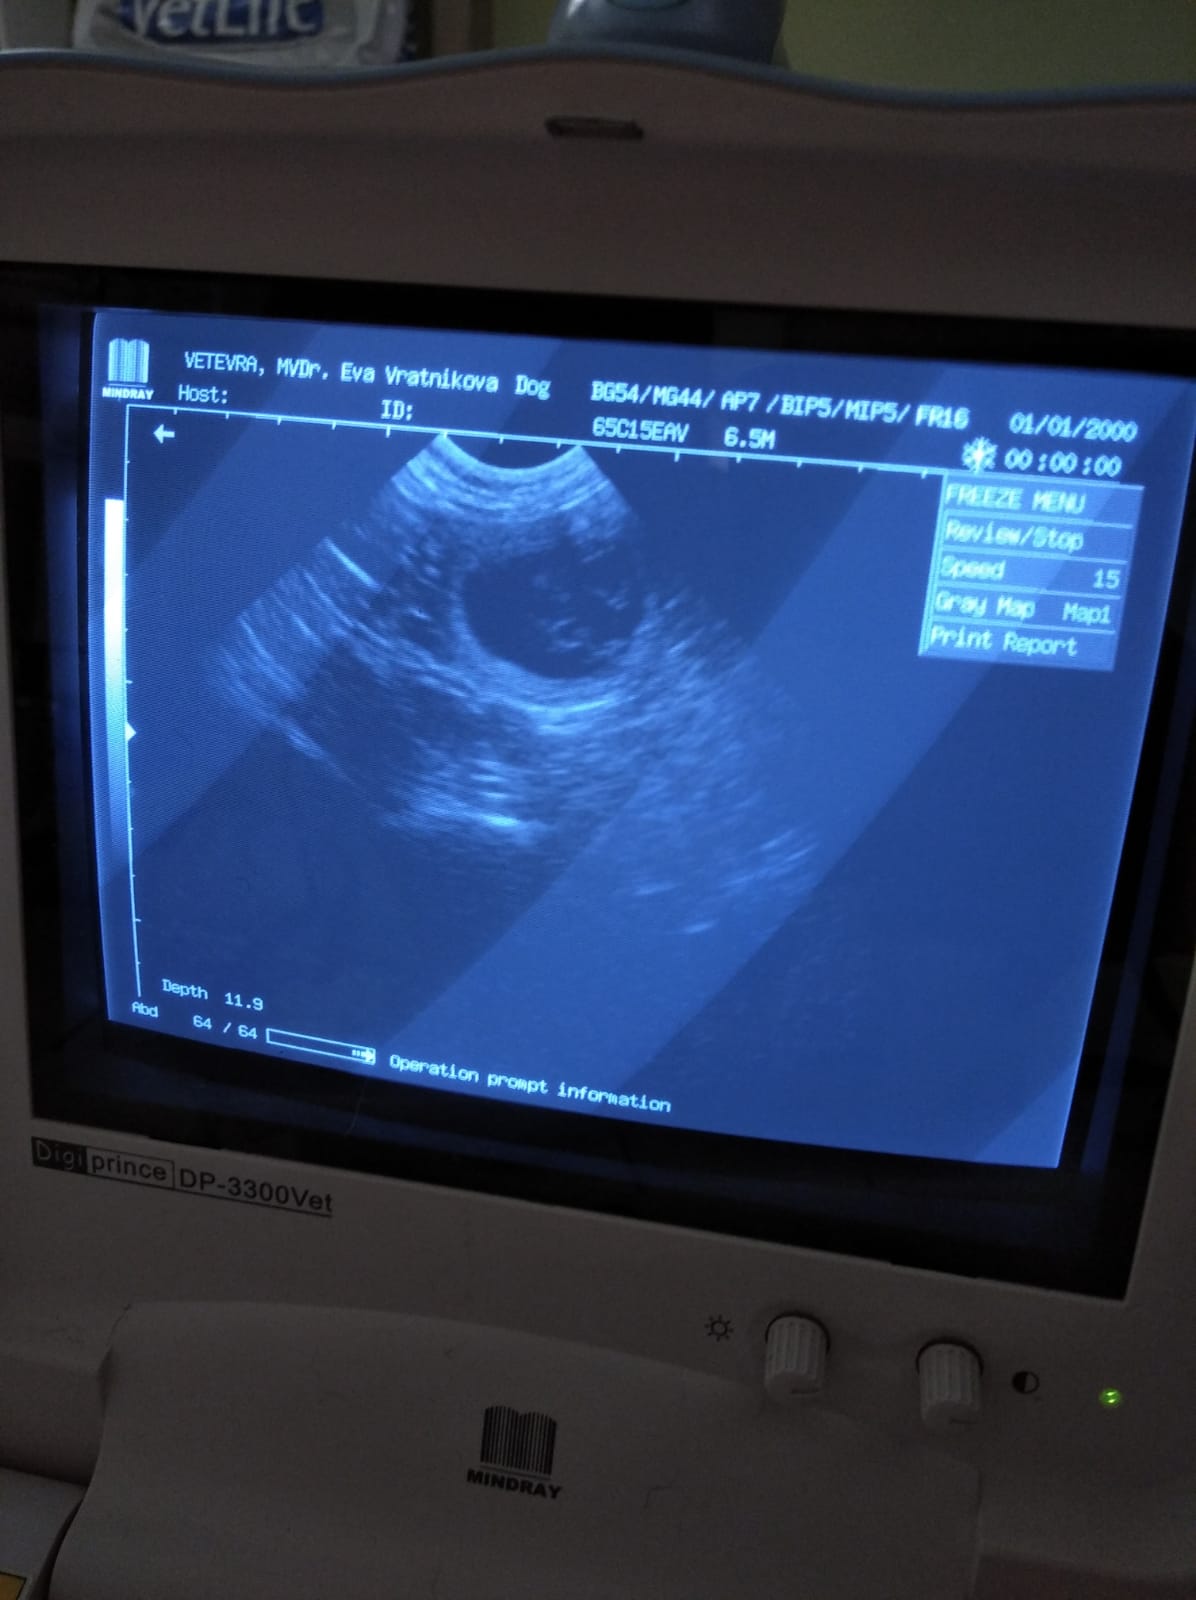

9.8. Potvrzení březosti